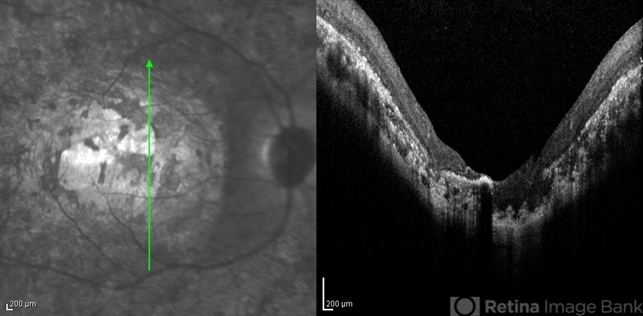

- infrared image, optical coherence tomography (OCT), macular coloboma

- Infrared and OCT images of the right eye of a 25-year-old woman with bilateral macular colobomata and pigmentary retinopathy similar to Leber's congenital amaurosis.